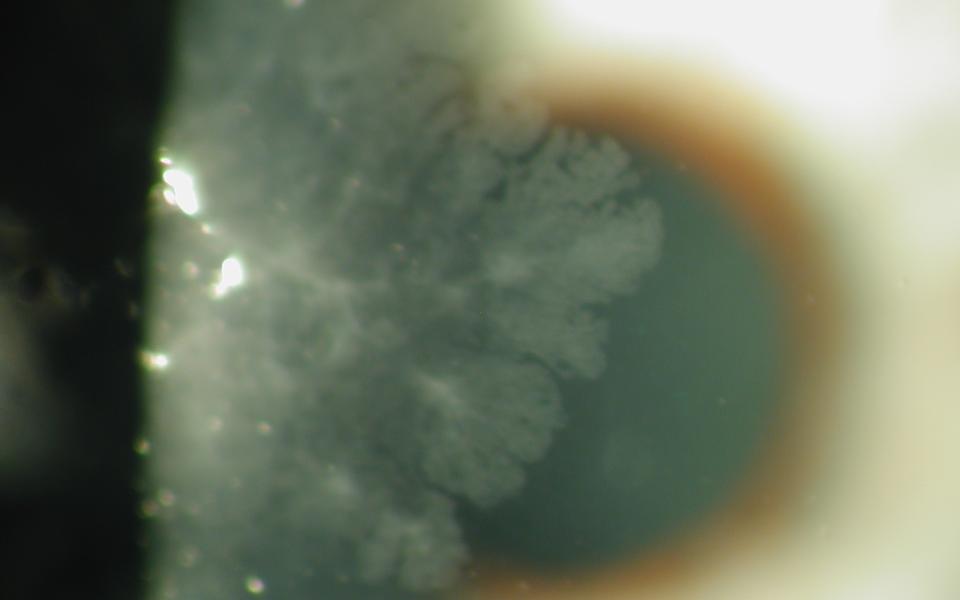

47yo female presented with unilateral reduction of vision in her right eye. Slit lamp examination revealed a anterior subcapsular cataract. The left eye showed early nuclear sclerosis only. On